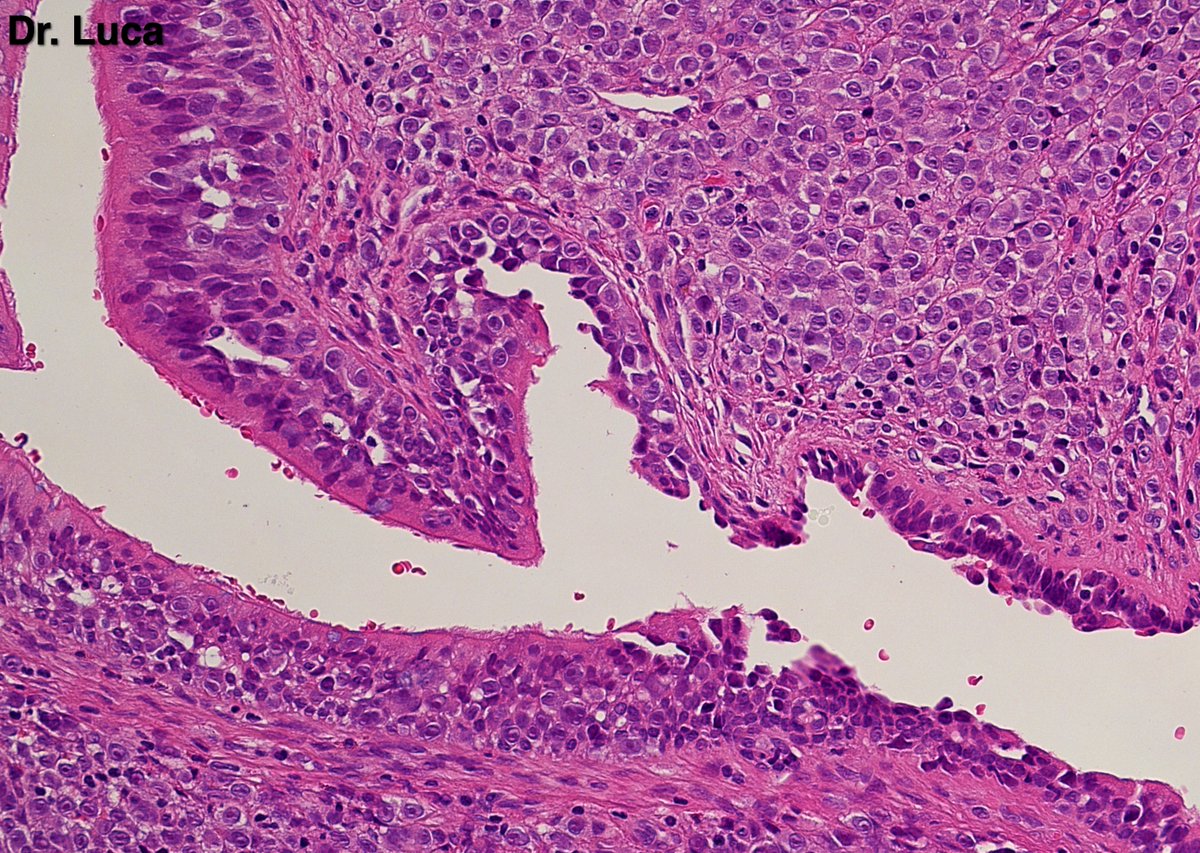

@Pathmath1 @SumantaDas_7 @PoloniaAntonio @ivanaspath @AnapathResident @bansar7 @goziemnweke @Teclis82 @Dr_Brian_Cox @DrBMcGinn @ariella8 @nusrat_xahra @DrRusella_Mirza @glinglerimek @kis_lorand @Venkateshgilly2 @DrBonita16 @DrPayelMondal @DrGeeONE @anjuthevirgo @niki_2389 @pepeheffernan @AngeloCassisa @NeoCrazee @TristanRutland7 Yes, it's a cancer with PNI...I show you the "superficial" layer of this cancer...what is the cancer? and what is the organ? #Pathology #GIpath #PathTwitter #PathResidents #pathboards

2

11